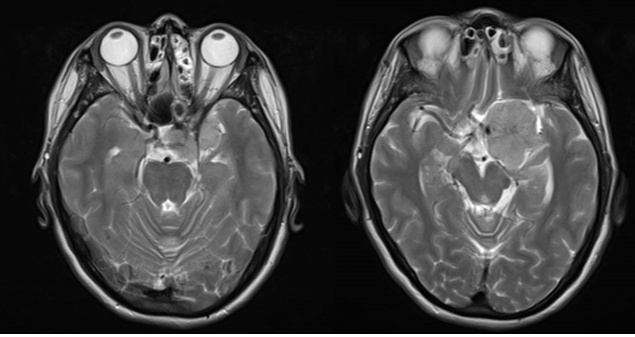

现病史:患者20天前无明显原因出现鼻酸,伴有异味感,继之出现全身不适,呈发作性,每次持续约1分钟左右,发作时意识清、精神可,对发病时情况记忆模糊,共发作3-4次,无意识模糊、复视。颅脑MRI平扫+强化示:鞍上池左侧可见不规则等T1等T2信号影,DWI呈等信号;明显均匀强化,与前床突、颈内动脉关系密切。

诊断:左侧蝶骨嵴脑膜瘤;继发性癫痫。

Al-Mefty教授根据肿瘤的起源和肿瘤与颈内动脉之间是否存在蛛网膜界面,将前床突-蝶骨嵴内侧的脑膜瘤分为三型,这是目前最为经典和广泛认可的分型。ICA在前床突内、下侧方从海绵窦穿出,经过内环与外环(或上环与下环)而后进入硬膜下腔,内外环之间约1-2mm,该节段缺少蛛网膜覆盖。起源于这一小段的脑膜瘤被分为1型前床突脑膜瘤。1型典型的生长方式是包裹ICA,并向颈内动脉分叉部方向生长,包裹近端大脑中动脉。由于肿瘤与颈内动脉之间缺乏蛛网膜,所以它紧密黏附在ICA的外膜上,以至于分离困难,导致手术治愈率相对较低。该患者主体属于1型前床突脑膜瘤,但是因其部分侵入视神经管内,兼有3型的特点,严格讲其属于1-3复合型脑膜瘤。该患者经左侧翼点入路肿瘤切除术,实现肿瘤近全切除,术后未再出现癫痫发作,脑电图无异常,后逐渐减用停用抗癫痫药物,现已持续随访4年余,未见肿瘤复发。